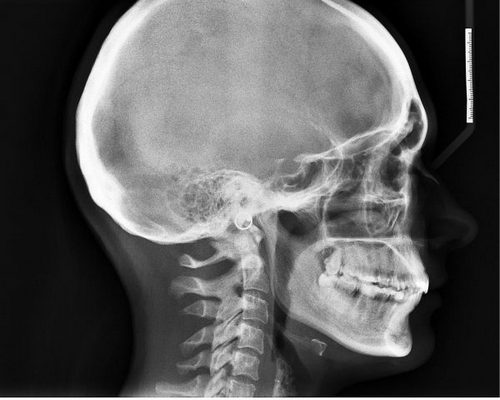

Безусловно, перед началом лечения крайне важно пройти профессиональную диагностику. С ее помощью удастся точно выяснить, с чем именно приходится иметь дело. Не стоит самостоятельно принимать медикаменты, потому как они могут оказаться неэффективны. Курс лечения должен быть назначен в зависимости от ситуации. Например, врач может направить пациента на МРТ и КТ. Эти исследования являются достаточно информативными и позволяют выявить многие патологии мозга. Также нередко назначают рентген, он особенно полезен в случае травм головы.